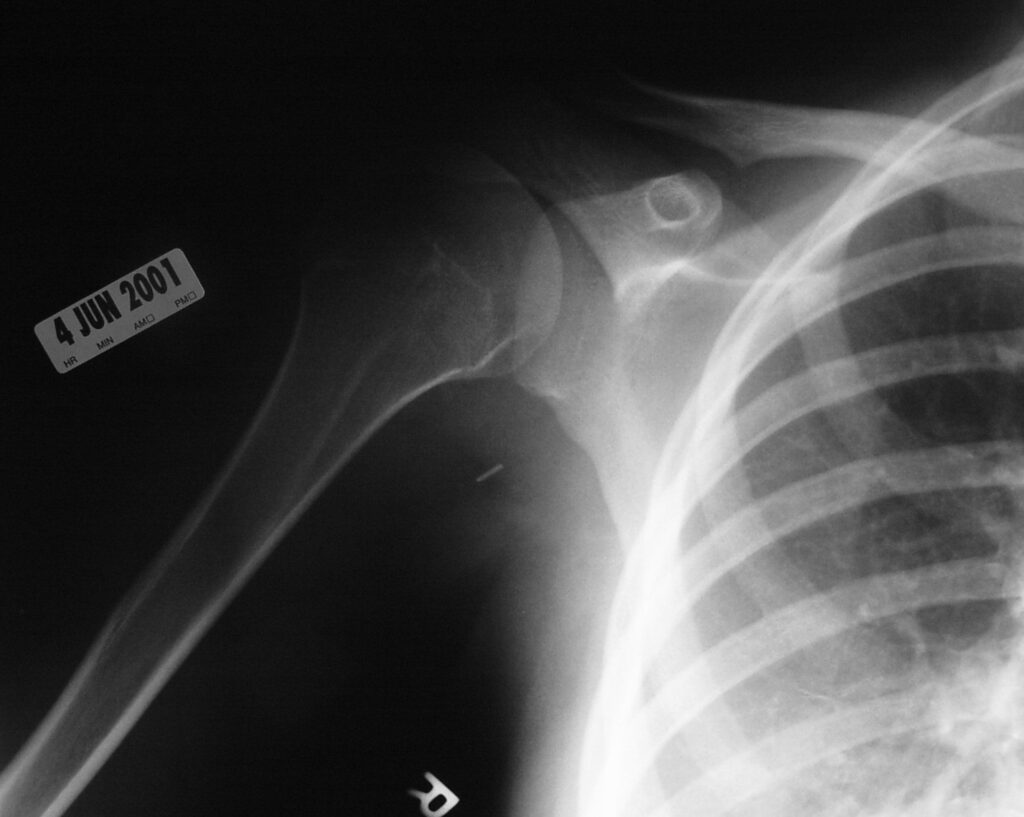

Synovial chondromatosis is an uncommon, benign, process that occurs in large joints, such as the knee (50%), hip, elbow, or shoulder. This process mainly affects synovium and hence most commonly arises from joints and tendons which are lined by synovium. Synovial Chondromatosis may also affect bursae and extend into surrounding soft tissues. This condition is seen in patients between 20 and 50 years of age and most commonly in men (male-female ratio of 2-4/1). The patient usually complains of pain, stiffness, crepitance, swelling, and joint locking. The knee is the most common site to be affected. Symptoms are long-standing and progressive. The plain x-ray may be normal (5 to 33%) or there may be small flecks of calcification (Fig. 1 & 2). On MRI the nodules of cartilage are easily seen. MR imaging may also show synovial thickening, joint erosions and intraarticular calcifications. The signal characteristics of these intraarticular bodies depend of their composition. If mineralization is not present the signal intensity follows the cartilage signal with intermediate signal on T1 images and high signal on T2 weighted MR images. Uniformly calcified bodies follows bone density on all sequences with bone marrow signal centrally and low signal peripherally (Fig. 3-5). Histologically the cartilage is arranged in nodules, which are quite cellular (Fig. 7-9). Synovial lining is present surrounding the cartilage nodules (Fig. 8). The cartilage nodules are often referred to as loose bodies however they are not really loose and embedded in the synovium lining. This is considered a metaplastic condition as opposed to a true neoplastic condition. Rarely it may turn into a malignancy usually a low grade chondrosarcoma. Malignant change is suggested by deep erosions into adjacent bone.

Fig. 1 & 2. Plain X rays of right shoulder synovial chondromatosis. AP (Fig. 1) and outlet (Fig. 2) views demonstrate multiple calcified bodies. Joint erosions are not seen on these x rays.